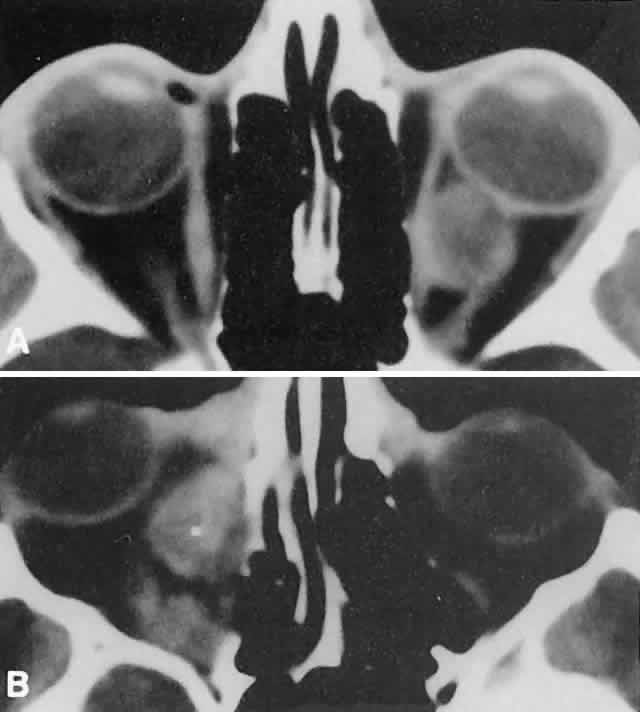

Orbital myositis may represent a greater proportion of cases of IIPT in childhood than in adulthood, and involvement of multiple extraocular muscles may occur more frequently in children than inadults. In orbital myositis, early diplopia and increased discomfort with attempted eye movement are typical symptoms. CT may show enlargement of one or more extraocular muscles in one or both orbits (Figs. 21 and 22). When a single muscle is involved, the specter of a primary or metastatic neoplasm within the muscle may be raised. However, external inflammatory signs, considerable pain and limited motility, and an explosive onset of symptoms within 24 hours all suggest orbital myositis. The uniform enlargement of the muscle, including its tendinous insertion (see Fig. 22), also helps distinguish the process from a neoplasm, which might be expected to produce a more focal, globular expansion. Echography may support the diagnosis of inflammation by showing edema in the episcleral space as a relative sonolucency between the scleral and orbital fat echoes (Fig. 23). Its CT counterpart is an increase in the radiodensity and thickness of the ocular tunica.

Fig. 21. A. This 16-year-old boy had acute onset of bilateral proptosis, pain, diplopia, chemosis, and conjunctival injection. B. Bilateral enlargement of the superior and medial rectus and inferior oblique muscles. Other sections showed similar involvement of other extraocular muscles.

Fig. 22. The uniform enlargement of the left medial rectus muscle, including its tendinous insertion, is characteristic of orbital myositis.

Fig. 24. A. Nonbacterial dacryoadenitis may be unilateral or bilateral. External inflammatory signs are maximal in the superotemporal quadrant. B. The left lacrimal gland is enlarged, with a shape molded by the globe and orbital walls. A neoplasm usually can be ruled out by analysis of the history, CT findings, and echographic characteristics, but a biopsy may be required in equivocal cases.